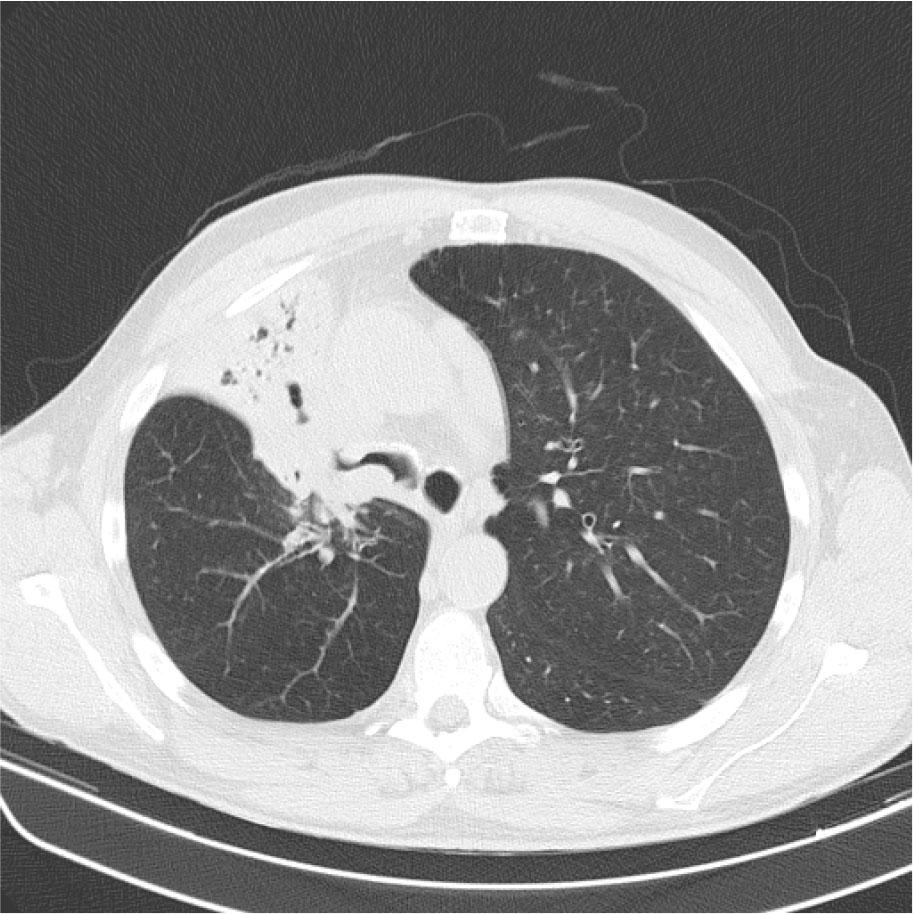

A 56-year-old male patient presented to the emergency department in September 2021 with complaints of cough, dyspnea, fatigue, and anorexia. He was an ex-smoker (23 pack-years) and had no relevant medical history. A chest X-ray was performed, which showed right perihilar hypotransparency with mediastinal shift and retraction of the hemidiaphragm. Thoracic computed tomography (CT) scan showed a lesion in the main right bronchus, with partial collapse of the right upper and middle lobes (figure 1). The patient underwent bronchoscopy, where an exophytic lesion was observed in the middle third of the main right bronchus. Bronchial biopsies revealed squamous cell lung cancer with negative PD-L1 expression. Brain magnetic resonance imaging (MRI) showed a left frontal superior lesion with contrast-enhancing and exuberant peripheral edema. The lesion was resected, and the histopathologic assessment was compatible with metastasis from squamous cell cancer. NGS was performed, and an insertion mutation in exon 20 of the EGFR gene was identified. After completing disease staging (TNM IVA, T2aN2M1a), chemotherapy with immunotherapy (carboplatin, paclitaxel, and pembrolizumab) was initiated in October 2021. The patient completed four cycles of treatment and showed stable disease according to the Response Evaluation Criteria in Solid Tumors (RECIST) criteria. Maintenance treatment with immunotherapy was started in January 2022. After three maintenance treatments, the patient showed progressive disease in the primary lesion according to RECIST criteria.

CT scan at diagnosis showing a right upper lobe lesion with right upper and medium lobes collapse.